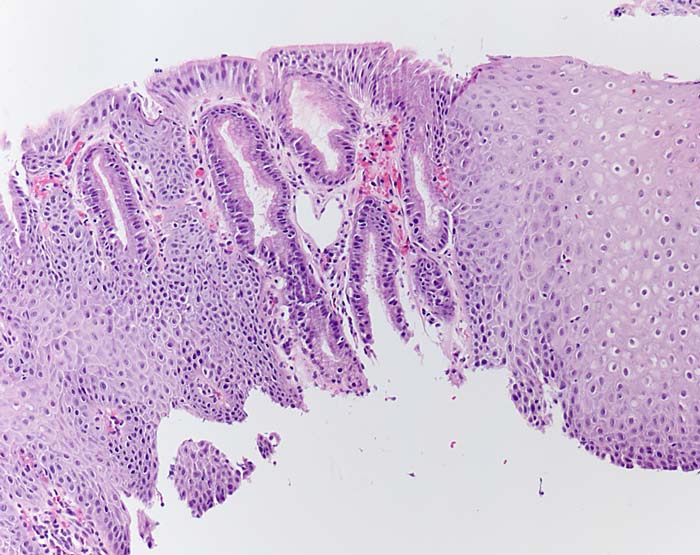

Reflux-Ösophagitis mit Zylinderzellmetaplasie

Die distale Ösophagusschleimhaut zeigt zwischen Plattenepithl eine kurzstreckige Zylinderzellmetaplasie ohne Becherzellen (Schleimhaut vom Kardiatyp ohne Becherzellen oder magenspezifische Drüsen) mit Einblutung. Leichte Hyperplasie der Basalzellen, aber kaum Entzündung.

Protonenpumpen-Inhibitor-Medikation. Refluxerkrankung Grad II.